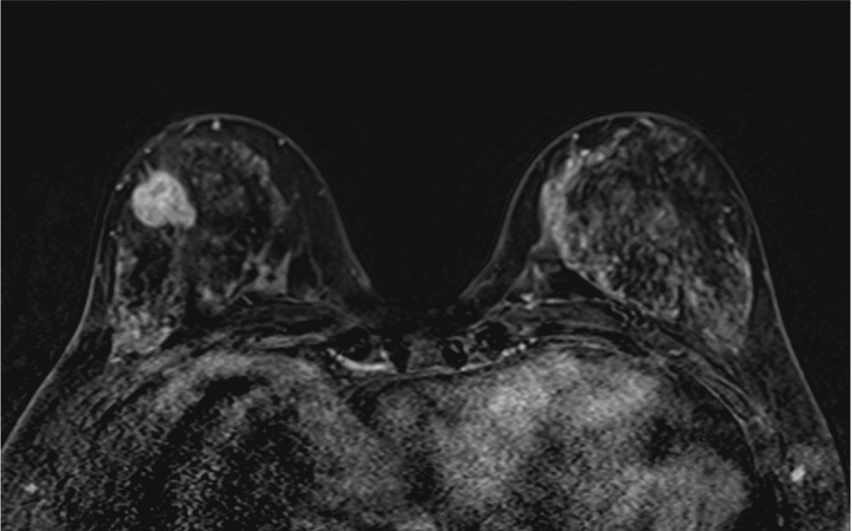

4. ダイナミックMRI (造影前 早期相 遅延相)

早期相で、乳腺の辺縁にBPE(矢印)を認めるが、その範囲は広くなくmildと判定する。乳癌の病変は、早期相から急速に造影され、遅延相でwash outがみられる。BPEは、遅延相で拡大し増強している。